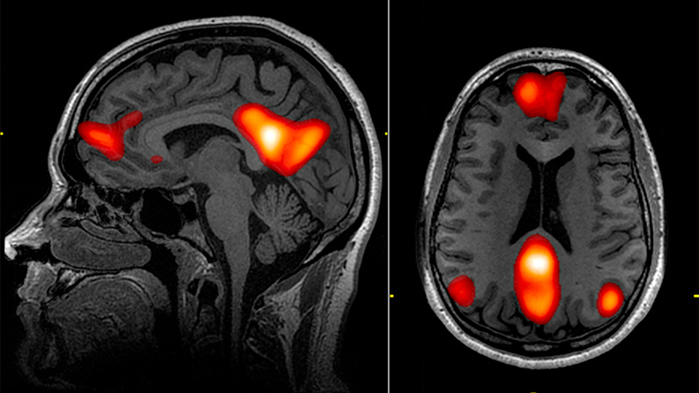

Anderson and his colleagues recruited 168 adult male prisoners to participate in an auditory oddball task, in which participants were instructed to click a button whenever they heard a particular tone. The auditory task was conducted inside a functional magnetic resonance imaging (fMRI) machine that measures activity in various regions of the brain.

The results showed that participants who scored higher on the psychopathy checklist also displayed abnormalities in brain regions associated with attention, including the anterior temporal cortex, medial prefrontal cortex, dorsal anterior cingulate, temporoparietal junction, and posterior cingulate cortex.

The study authors suggest psychopathy might be caused by an inability of different functional networks of the brain to integrate properly. For example, psychopaths might not be able to efficiently switch from a wakeful rest state (default mode) to one in which they can readily make decisions.